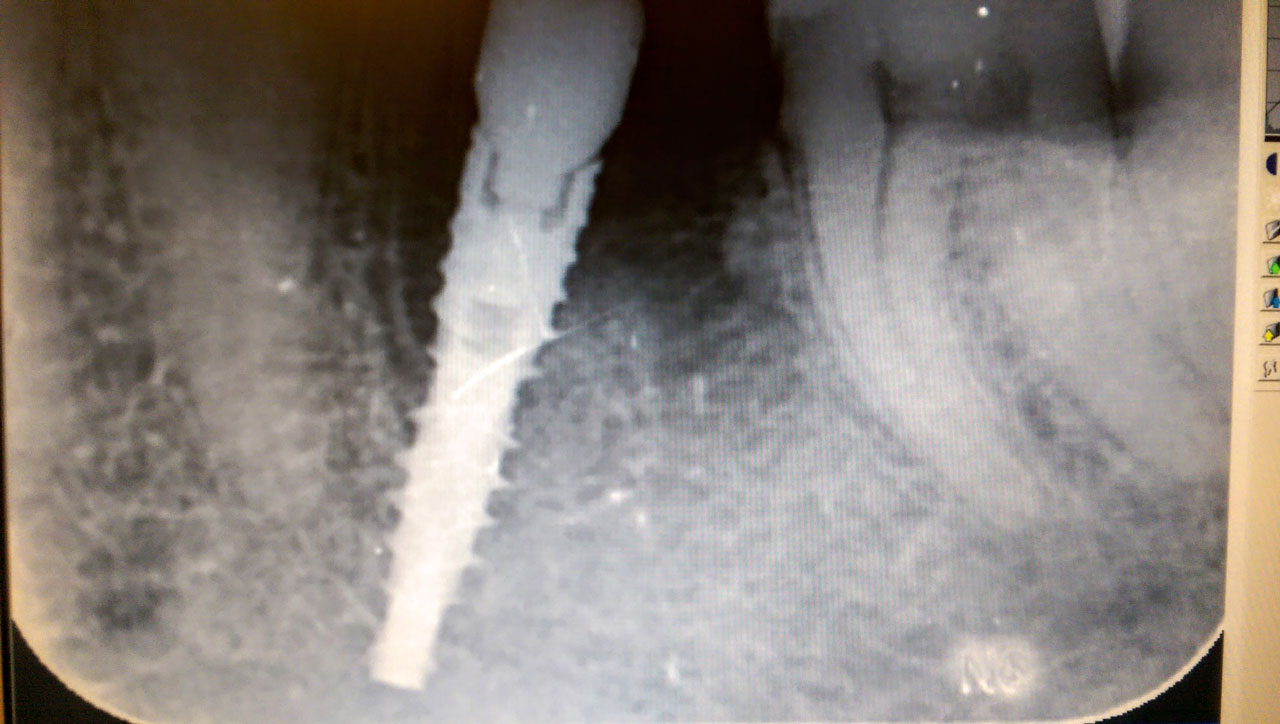

Alsó állcsont teljes rehabilitációja 72 óra alatt, azonnal terhelhető implantátumokkal súlyos paradontitisben szenvedő dohányzó páciens esetében. Az alsó állcsont fogai mind mozogtak az előrehaladott fogágypusztulás miatt.

A fogakat eltávolítottuk, a gyulladt, fertőzött csontot kitakarítottuk, kifertőtlenítettük, majd azonnal implantáltunk.

Svájci, IHDE márkájú, azonnal terhelhető implantátumokat helyzetünk be, és ezekre harmadnapra rögzített, hosszútávú, fémvázas, esztétikus műanyaggal leplezett hidat ragasztottunk be.

Ezt az ideiglenes hidat a sebek gyógyulása miatt használjuk, de tartóssága miatt véglegesként is használható. A legtöbb esetben, ahogy itt is, 6 hónap múlva porcelán hídra cseréljük, a teljes gyógyulás után.